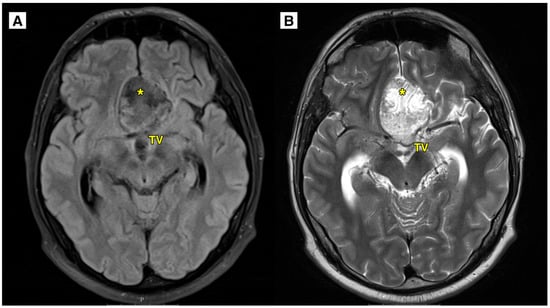

2.2. Imaging Findings